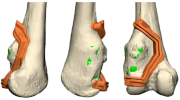

| 14:06, 14 באוגוסט 2023 | תבנית חיתוך3.png (קובץ) |  |

574 קילו־בייטים | Motyk | 1 | |

| 14:03, 14 באוגוסט 2023 | תבנית חיתוך1.png (קובץ) |  |

572 קילו־בייטים | Motyk | 1 | |